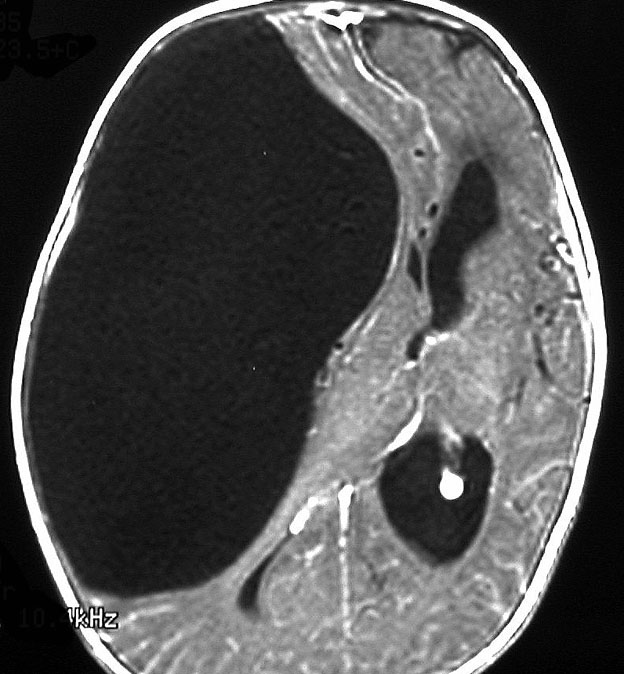

生後5ヶ月の女児に発生した右中頭蓋窩から海綿静脈洞から側頭下窩の成熟奇形腫です。腫瘍のう胞が大きく,右大脳半球の高度の圧排変形がみられます。

のう胞が巨大なので,まずのう胞腹腔シャントをして脳の変形を戻しました。その2ヶ月後に開頭手術で腫瘍を亜全摘出しています。